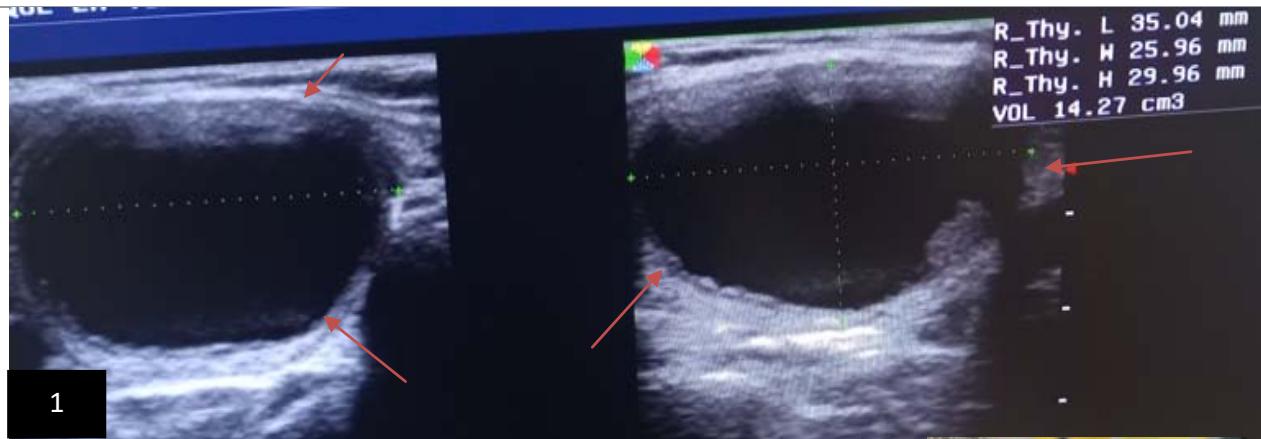

Iconography A: 1. Ultrasonographic image in B mode, showing a uniloculated cyst, EU-TIRADS 2 of 14.27 ml before sclerotherapy;

2. Ultrasonographic image in B mode after first sclerotherapy session, 3. Ultrasonographic image in B mode, after the second sclerotherapy session, showing complete drying of the cystic nodule, 4. image showing the sero-hematic content of the drained and alcoholic cyst.